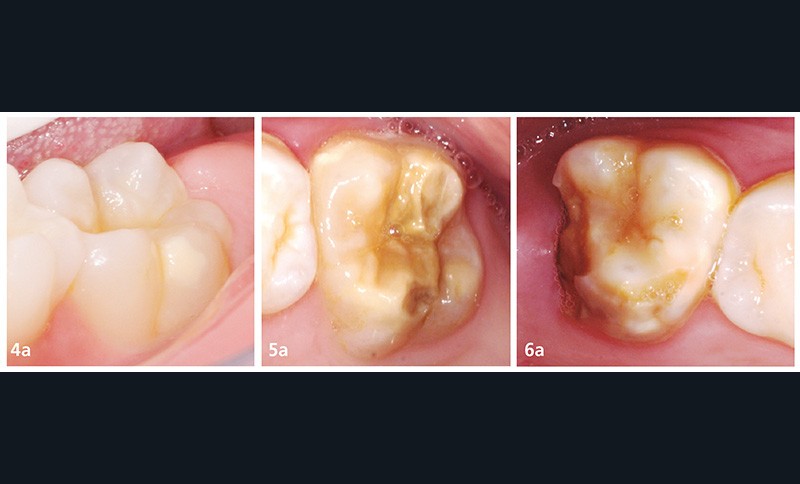

Si elle est légère (fig. 4a et b) :

– surveillance ;

– fluoration biannuelle (> 22 500 ppm) ;

– scellements de sillons.

Si elle est modérée (fig. 5a et b) :

– fluoration biannuelle ;

– scellement de sillons ;

– restauration directe au composite (marge saine) ;

– restauration directe aux verres ionomères ;

– restauration indirecte partielle collée (marge saine).

Si elle est sévère (fig. 6a et b) :

– restauration par coiffe pédiatrique préformée (CPP) ;

– en cas d’échec des thérapeutiques restauratrices : avulsion. Décision pluridisciplinaire entre chirurgien-dentiste et orthodontiste (si présence de la 8, en fonction de la classe d’Angle et de la typologie faciale).